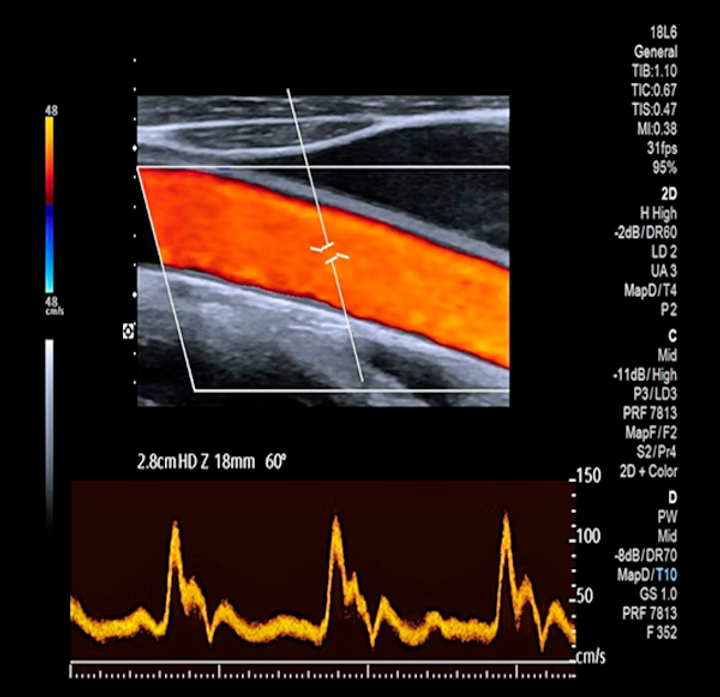

2️⃣ Color Doppler : remplissage homogène, absence de turbulence.

3️⃣ Spectral Doppler : profil phasique = flux veineux sain, triphasique = flux artériel normal.